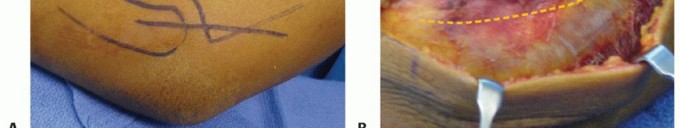

A 5-cm oblique incision is made from the posterolateral aspect of the lateral epicondyle obliquely to a point three fingerbreadths below the tip of the olecranon in line with the radial neck (TECH FIG 1A).

- TECH FIG 1 • Kocher approach. A. The skin incision proceeds distally from the posterolateral aspect of the lateral epicondyle to the posterior aspect of the proximal radius. B. Fullthickness flaps are made and the fascial interval between the extensor carpi ulnaris and anconeus muscles is identified. C. With longitudinal incision of the fascia and blunt division of the muscles, the joint capsule is evident. D. The capsule is longitudinally incised, and the fascia is tagged with figure-8 stitches for later anatomic repair.

The radial head and epicondyle are palpated, and the fascia is divided in line with the skin incision.

The Kocher interval is identified distally by small penetrating veins and bluntly developed, revealing the lateral ligament complex and joint capsule (TECH FIG 1B).

The anconeus is reflected posteriorly and the extensor carpi ulnaris origin anteriorly. The capsule is incised obliquely anterior to the lateral ulnar collateral ligament (TECH FIG 1C,D).

The proximal edge of the annular ligament may also be divided and tagged, with care taken not to proceed distally and damage the posterior interosseous nerve. -

An 8-cm straight longitudinal incision is made just lateral to the olecranon (TECH FIG 2A). Full-thickness skin flaps are developed bluntly over the fascia.

The fascia is longitudinally incised in the interval between the anconeus and ulna (TECH FIG 2B).

The anconeus is dissected off the ulna, elevating proximal to distal to preserve the distal vascular pedicle. Great care is taken not to violate the joint capsule or lateral ulnar collateral ligament by using blunt fashion (TECH FIG 2C).

The lateral ulnar collateral ligament and annular ligament complex are sharply divided and tagged from

their insertion on the crista supinatoris of the ulna. The radial head and its articulation with the capitellum are now evident (TECH FIG 2D).

After repair or replacement, the ligaments are repaired to their insertion with suture anchors.

- TECH FIG 2 • Modified Wrightington approach. A. Make an 8-cm longitudinal incision at the junction of the ulna and anconeus starting about four fingerbreadths distal to the olecranon and extending 2 cm proximal to the olecranon. (continued)

TECH FIG 2 • (continued) B. The interval between the ulna and anconeus is incised sharply, with care taken not to violate the periosteum or muscle to minimize the risk of proximal radioulnar synostosis. C. Blunt elevation of the anconeus is crucial to avoid damaging the capsule or lateral ligament complex. D. The capsule and lateral ligament complex are tagged during the approach to facilitate final repair with suture anchors.